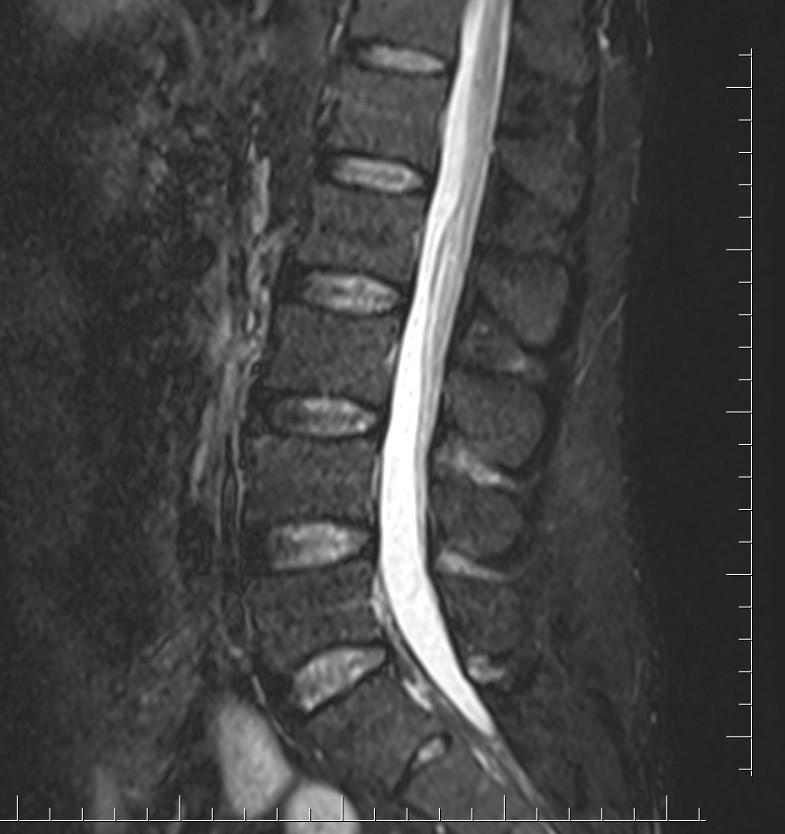

Case of the Week 14 2017 *49-year-old male. What is the most likely diagnosis? Answer Answer: Filum terminale lipoma Kategori:Cases Önceki yazı Case of the Week 17 2017 Sonraki yazı Case of the Week 18 2017